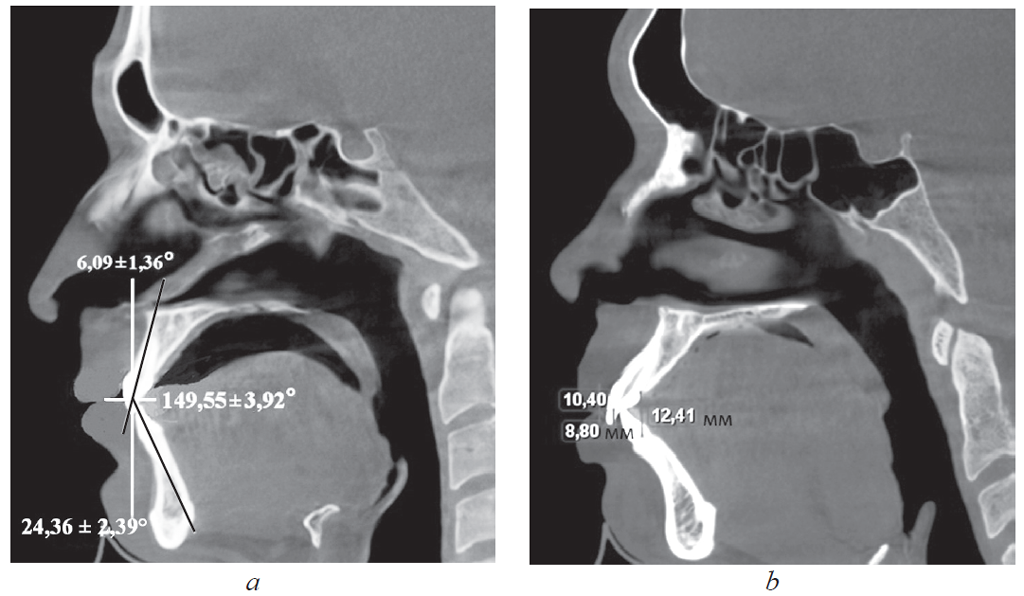

Материал и методы. Обследованы 62 человека первого периода зрелого возраста в двух клинических группах. В 1-ю группу вошли 24 пациента с физиологической окклюзией, а во 2-ю (38 человек) — с патологической окклюзией. В каждой группе были выделены пациенты с протрузией и ретрузией резцов. Вертикальное перекрытие оценивали на томограммах и гипсовых моделях челюстей между горизонтальными линиями, проходящими через режущие края резцов верхней и нижней челюстей параллельно окклюзионной плоскости.

Результаты. У пациентов 1-й группы с протрузией резцов межрезцовый угол составил 149,55 ± 3,92°, торк верхних резцов — 24,36 ± 2,39°. При ретрузии резцов величина межрезцового угла составила 151,47 ± 2,94°, торк верхних резцов — 5,85 ± 1,42°. При этом величина вертикального перекрытия соответствовала величине сагиттального перекрытия и не превышала 2–3 мм. У пациентов 2-й группы, как правило, отмечалось нарушение формы зубных дуг в переднем отделе.

Выводы. Для диагностики физиологической протрузии или ретрузии резцов использовали величины перекрытия в сагиттальном и вертикальном направлениях, которые соответствовали друг другу и не превышали 3 мм.